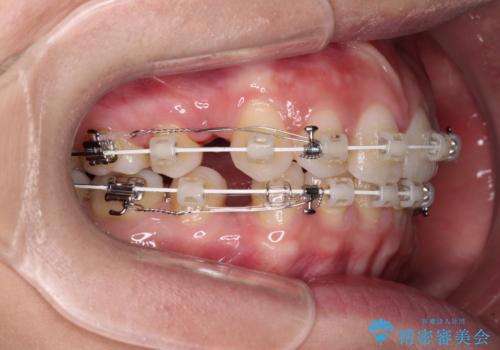

- 矯正装置

- 審美装置

- 1年7ヶ月

- 10-30回

上下左右第一小臼歯4本を抜歯して、積極的に口元を引っ込めるよう、ワイヤー装置にて矯正治療を行うこととしました。